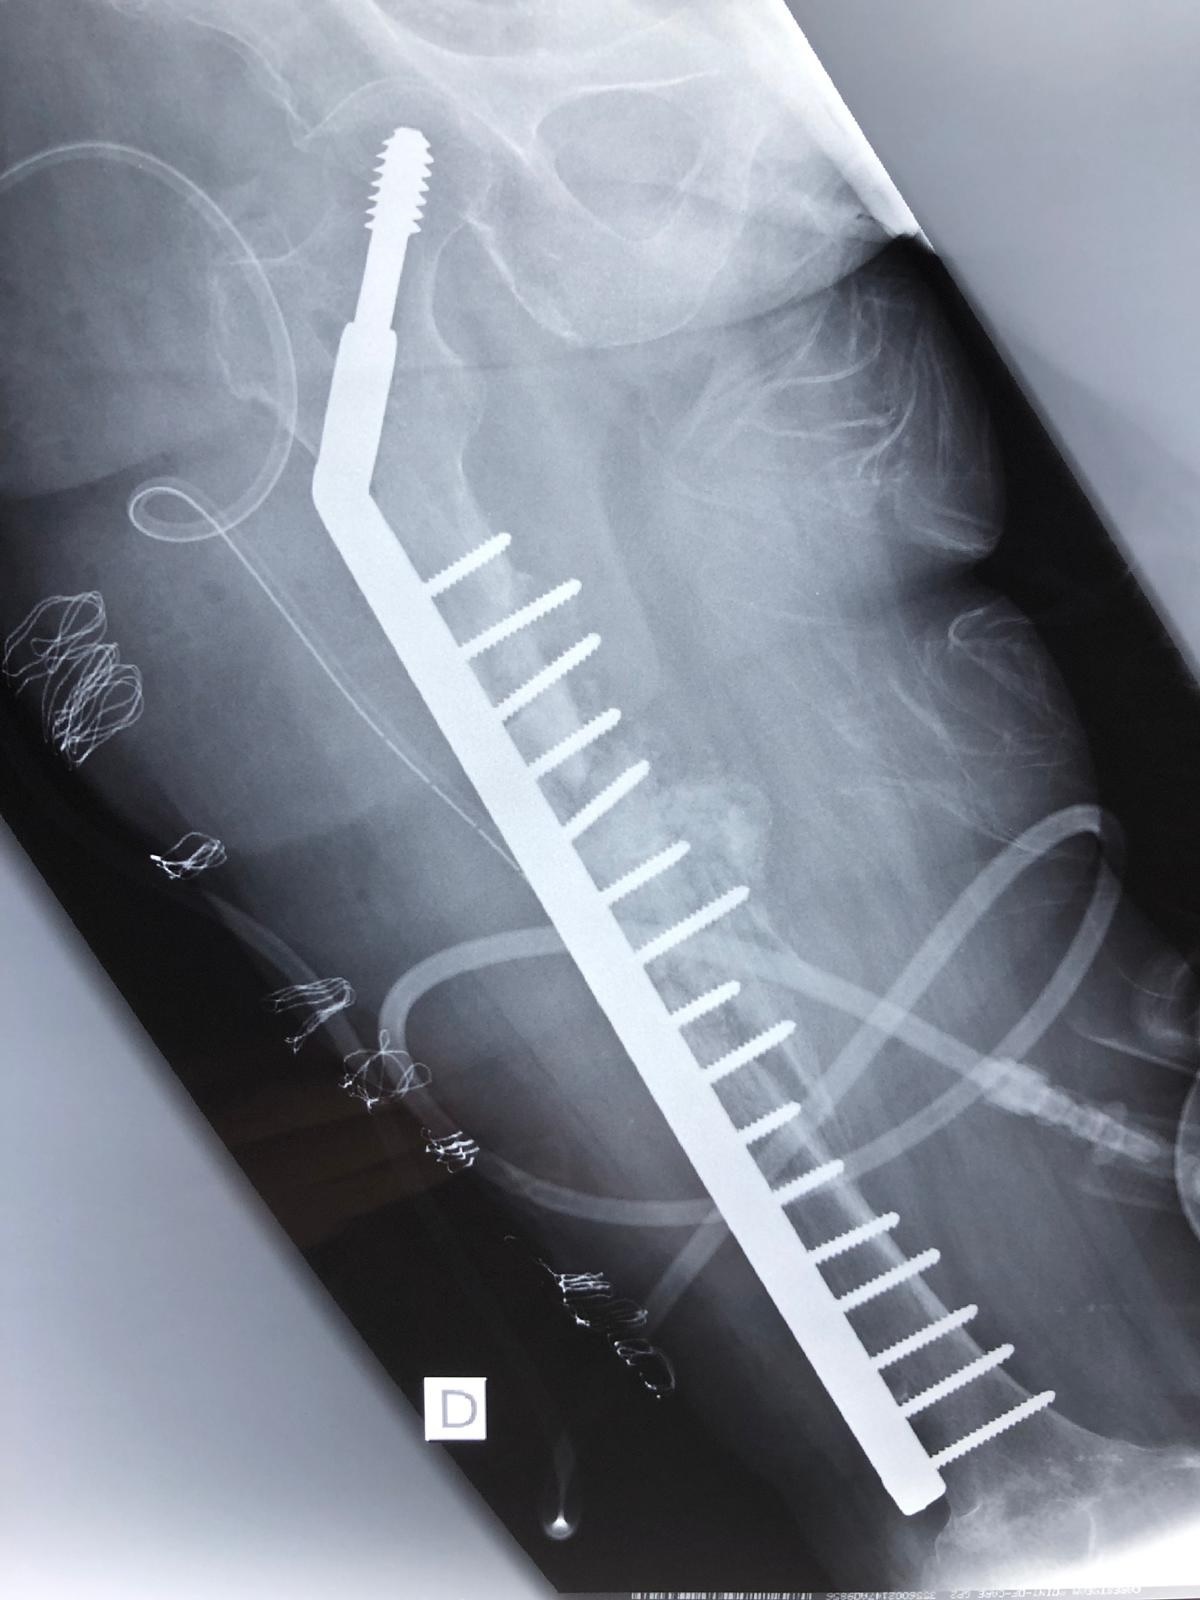

Die Fortbewegung war nur krabbelnd und hüpfend möglich. Im Röntgenbild sah man Residuen der Tibiakopffraktur sowie eine Verkalkung im Bereich der dorsalen Kapsel. Es erfolgte eine Arthrolyse des Kniegelenkes ventral und dorsal, gefolgt von einer redressierenden Gipsanlage (Abb. 4), wodurch die Beugekontraktur auf eine ROM von 0 – 20 – 110° erweitert werden konnte. Die verkürzte Muskulatur wird jetzt physiotherapeutisch behandelt und der Patient war zum Abschluss der Behandlung gehfähig. Ein zweiter wesentlicher Part der chirurgischen Tätigkeit stellte die Revision unzureichender Heilungsergebnisse dar. Die Ursachen hierfür waren heterogen. Fehlende Verfügbarkeit geeigneten Materials und unzureichende Nachbehandlung standen hierbei im Vordergrund. So auch bei unserem 2. Fallbeispiel, einer 51-jährigen Dame, die vor einem Jahr eine Oberschenkelfraktur erlitten hatte und mittels Nagelosteosynthese versorgt wurde. Dieser wanderte proximal aus und bei bestehender Pseudarthrose erfolgte eine Plattenosteosynthese. Leider wurde zur postoperativen Immobilisation eine Mecron-Schiene in Kombination mit einem Rollstuhl gewählt, bei dem leider keine Abstützung des Beines möglich war. So hebelte die Schiene direkt am Ende der Platte und es kam zu einer Anschlussfraktur (Abb. 5) oberhalb der Platte. Diese wurde durch uns revidiert und mit einer DHS mit 16 Löchern ersetzt (Abb. 6). Hierunter konnte letzten Endes eine ausreichende Stabilisierung erreicht werden.